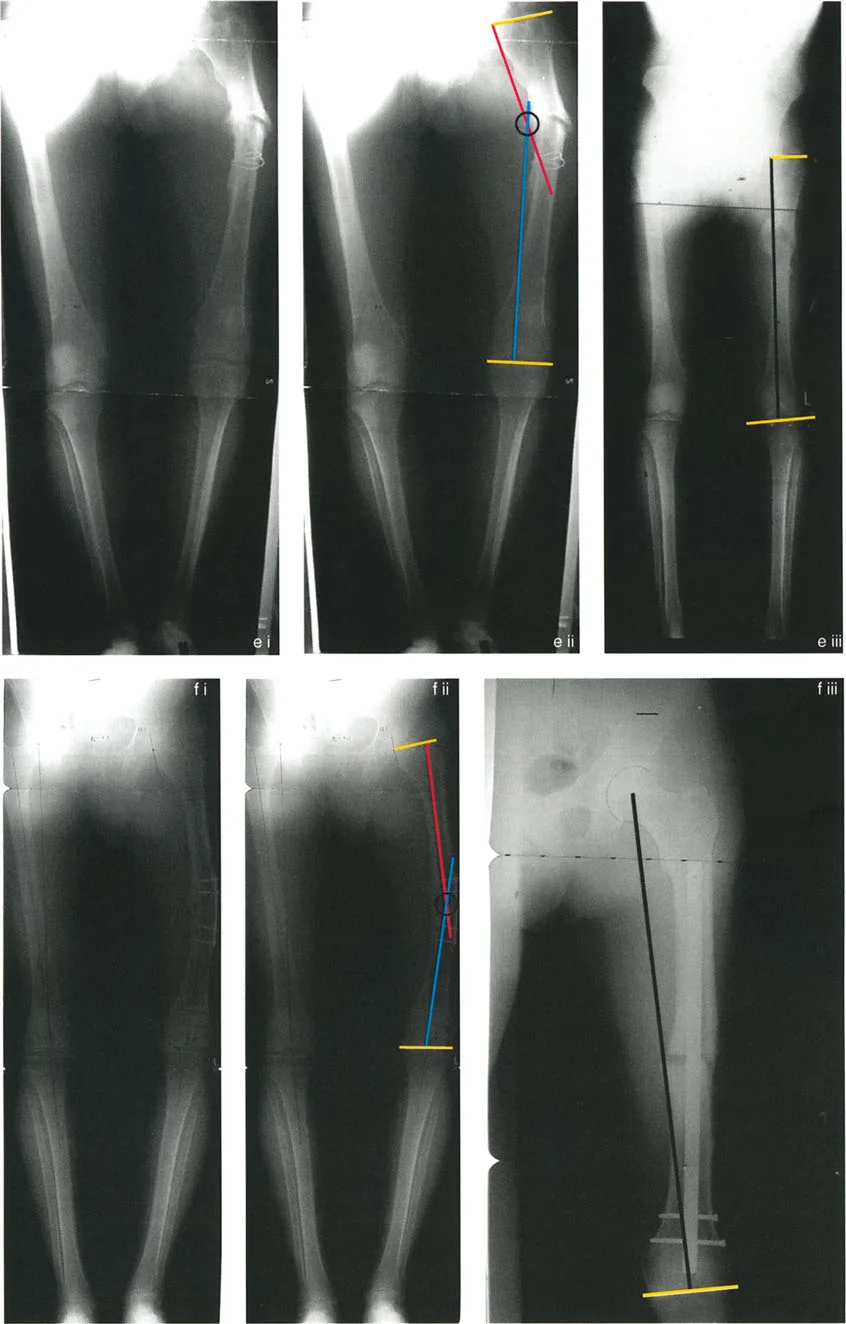

To determine exactly where the deformity lies (femur versus tibia, proximal versus distal), the surgeon must perform the Malorientation Test. This involves measuring specific joint orientation angles and comparing them to established normal population values.

Femoral Joint Orientation Angles

The femur is evaluated by drawing the mechanical axis of the femur (from the center of the femoral head to the center of the knee) and measuring its intersection with the joint lines.

- mLDFA (mechanical Lateral Distal Femoral Angle) This is the lateral angle formed between the mechanical axis of the femur and the distal femoral joint line. The normal value is 87 degrees, with a standard range of 85 to 90 degrees. An mLDFA greater than 90 degrees indicates a distal femoral varus deformity. An mLDFA less than 85 degrees indicates a distal femoral valgus deformity.

Center of Rotation of Angulation

The Center of Rotation of Angulation (CORA) represents the apex of the deformity. To find the CORA, the surgeon draws the Proximal Mechanical Axis (PMA) line and the Distal Mechanical Axis (DMA) line.

* The PMA is drawn by taking the normal joint orientation angle from the proximal joint and extending a line down the shaft.

* The DMA is drawn by taking the normal joint orientation angle from the distal joint and extending a line up the shaft.

* The exact point where the PMA and DMA intersect is the CORA.

A bone may have a single CORA (unapical deformity) or multiple CORAs (multi-apical deformity). Identifying the precise location of the CORA is the prerequisite for determining where to cut the bone and how to hinge the correction.

While the CORA is a fixed geometric point dictated by the patient's pathology, the Axis of Correction of Angulation (ACA) is the actual hinge point around which the bone segments are rotated during surgery.

The placement of the ACA is entirely under the surgeon's control. It can be placed on the convex cortex, the concave cortex, or even outside the bone entirely (as seen with external fixator hinges). The spatial relationship between the ACA and the CORA dictates the final alignment of the limb, the presence of translation, and changes in limb length.

Osteotomy Rule Two Angulation with Translation

The Geometric Definition

When the ACA passes through the CORA, but the osteotomy line is made at a different level (either proximal or distal to the CORA).

The Biomechanical Result

The mechanical axis and joint orientation angles are perfectly restored. However, because the bone cut is made at a distance from the hinge point, the bone segments will mathematically translate relative to one another. This creates a visible "bump" or step-off in the anatomic axis. While the bone looks jagged on an x-ray, the load-bearing mechanical axis is flawless.

Clinical Application

Rule Two is frequently used for juxta-articular deformities. For example, if a patient has a severe distal femoral valgus deformity, the CORA may be located inside the knee joint. A surgeon cannot perform an osteotomy through the articular cartilage. Therefore, the surgeon must place the ACA at the joint (the true CORA) but perform the actual bone cut (osteotomy) safely in the metaphysis.

The resulting translation is not an error; it is a necessary and mathematically sound compromise to achieve a straight mechanical axis while cutting the bone in a biologically safe zone.

Executing the Preoperative Plan

- Perform the Malalignment Test Draw the mechanical axis from the center of the femoral head to the center of the ankle. Measure the MAD. Determine if the mechanical axis falls in the medial, lateral, or central zone of the knee.

- Perform the Malorientation Test Draw the individual mechanical axes of the femur and tibia. Measure the mLDFA, MPTA, LPFA, and mLDTA. Compare these to normal values to isolate the source bone of the deformity.

- Locate the CORA Draw the Proximal Mechanical Axis (PMA) and Distal Mechanical Axis (DMA) using the normal joint orientation angles. Mark their intersection as the CORA.

- Select the Osteotomy Rule Determine if the bone can be safely cut at the CORA (Rule 1) or if the cut must be moved to the metaphysis (Rule 2).

Juxta Articular Deformities

Deformities located very close to the joint line present a unique challenge. The CORA is often located within the epiphysis or the joint space itself.

- Surgical Pearl You cannot cut through the CORA in these cases. You must utilize Paley's Rule 2. Place your hinge (ACA) at the joint line (the CORA), and perform your osteotomy in the metaphyseal bone.

- Managing Translation Be prepared for the resulting translation. When using a plate for fixation, you may need to use a specialized offset plate or manually contour the plate to accommodate the step-off. If using an intramedullary nail, blocking screws (Poller screws) are essential to guide the nail and maintain the translation without allowing the bone to slide back into deformity.